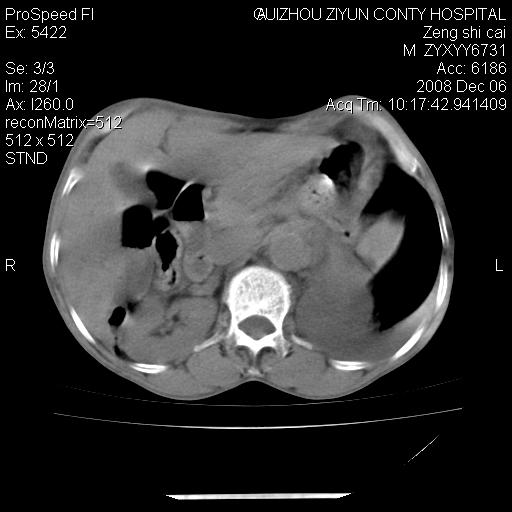

标题: CT16961:M、71岁,咳嗽半年,无血痰;胸片示右肺占位。 [打印本页]

标题: CT16961:M、71岁,咳嗽半年,无血痰;胸片示右肺占位。

1)考虑右肺上叶纵隔型肺癌伴纵隔淋巴结转移。2)心包积液,双侧胸腔积液。

升结肠癌伴腹膜后淋巴结转移

右肺癌并纵隔淋巴转移,腹膜后转移可能性大,两侧胸腔积液

右肺上叶纵隔型肺癌伴纵隔淋巴结转移。心包积液,双侧胸腔积液。